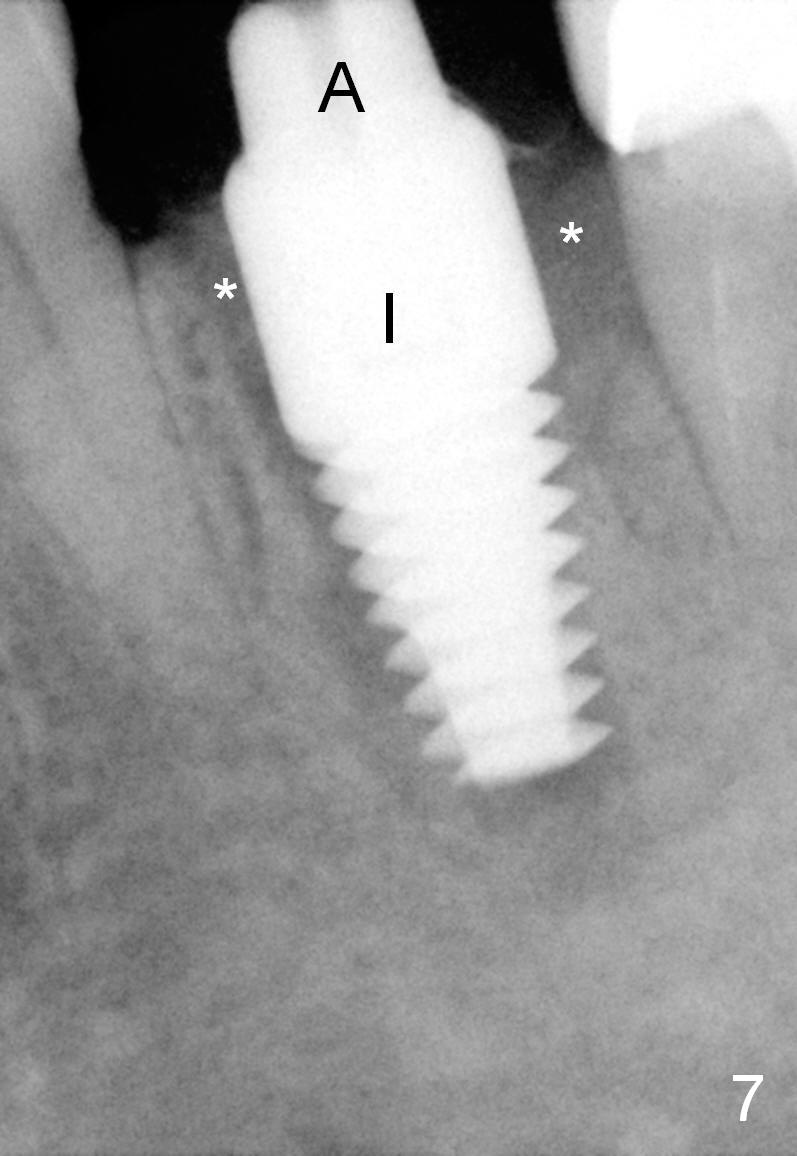

A 47-year-old lady lives out of town and presents to clinic with chief complaint "lower left back tooth easily bleeding with food impaction". Dental history and examination reveals failure of endo retreat of the tooth #19 (Fig.1), buccal gingival swelling (S), open access (A) and furcal and mesial periapical radiolucency (Fig.2 *). She is pleased to know availability of immediate implant and immediate provisional and accepts and receives the treatment at the same visit. The immediate implant (tissue-level) is designed to be as large as 7 mm and as long as 17 mm (Fig.3). To reduce paresthesia (yellow dashed line: the possible upper border of the Inferior Alveolar Canal)), a shorter implant (14 mm long in red line) is preferred. The tooth is extracted with sectioning. Granulation tissue is removed from the furca. The buccal plate appears to be intact. The septum is flat (Fig.4,10a S). Osteotomy starts in the middle of the septum with a 1.2 mm drill (Fig.10b red circle). As osteotomy increases in diameter (Fig.5 O), the apical end appears to be deviated mesiobuccally (Fig.10c large red circle). When a 6x17 mm tapered tap is being placed 14 mm deep (Fig.6 T), vibration of the buccal plate is seemingly felt at the apex (Fig.10d green circle). Further osteotomy may perforate the buccal plate. A 6x14 mm tissue-level implant is placed with >60 Ncm of insertion torque (Fig.7,8 I), followed by a 5x3 mm abutment (A) and bone graft (* in the remaining socket gap). An immediate provisional is cemented without occlusal contact (Fig.9 P).

Buccal gingival swelling and mesial periapical radiolucency suggests weakened buccal plate. Osteotomy in the septum should be initiated more lingually (Fig.10e). When the osteotomy starts being deviated, correct as early as possible with a Lindamann bur and preferably over-correct (Fig.10f blue circle). The final implant placement may not encroach the buccal plate (Fig.10f red circle). Three weeks postop, the buccal infection dissolves (Fig.11). What has not disappeared is the buccal undercut (*): the basis for potential buccal perforation. Buccolingual osteotomy trajectory should be adjusted intraoperatively accordingly.